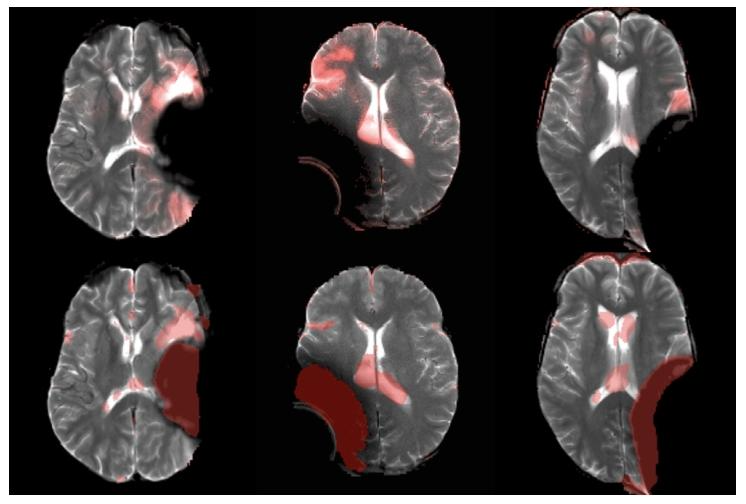

Fig. 7. Visualization of artifact detection results on our private dataset usingDAE (Kascenas et al., 2022) (top row) and our method 𝐼 𝑡𝑒𝑟𝑀𝑎𝑠𝑘3𝐷 (bottomrow). The final anomaly map is overlaid in red on the original image. DAEis shown to detect the hyper-intense area (mostly in normal brain area) asanomaly, while our method better detects the actual anomalous artifact.

图7 采用DAE方法(Kascenas等,2022)(上行)与所提方法IterMask3D(下行)在私有数据集上的伪影检测结果可视化 最终异常图以红色叠加显示在原始图像上。结果显示,DAE方法会将高信号区域(多为正常脑区)误检测为异常,而所提方法能更准确地检测出真实的异常伪影。